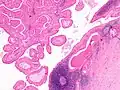

The appearance of this tumor under the microscope is unique. There are cystic spaces surrounded by two uniform rows of oncocytes, which are epithelial cells with abundant, granular, eosinophilic cytoplasm.[7] The cystic spaces have epithelium referred to as papillary infoldings that protrude into them. Additionally, the epithelium has lymphoid stroma with germinal center formation.

Histopathology of Warthin tumor in the parotid gland. H&E stain. -

Histopathology of Warthin tumor in the parotid gland. Another view of a file "Warthin tumor (1).jpg". H&E stain. -

Histopathology of Warthin tumor in the parotid gland. Higher magnification of a file "Warthin tumor (1).jpg". H&E stain. -

Intermediate magnification micrograph of a Warthin tumor. -